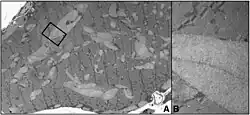

![]() | |

A rendering of the human muscular form of phosphofructokinase. Mutations in the production of this enzyme are the cause of Tarui's disease.[3] The symmetry of the enzyme is a result of its tetrameric structure. | |